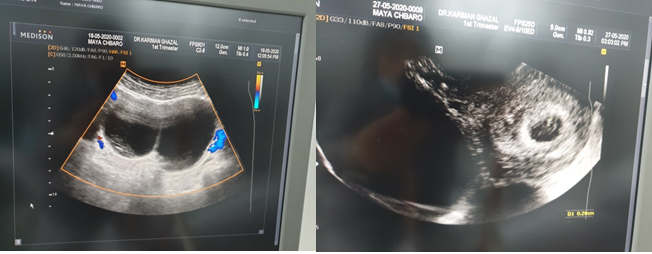

Case 3: A 26-year-old patient presented with severe pain, nausea and vomiting, and amenorrhea. Her pregnancy test was positive. Pelvic ultrasound showed right ovarian cyst fluid with septum negative Doppler at 7 weeks (Figure 3). She was given treatment with progesterone for 4 weeks. She had regression of the cyst after 11 weeks.

Figure 3 Pelvic ultrasound showing ovarian cyst >5cm with septum negative Doppler and gestational sac at 7 weeks.